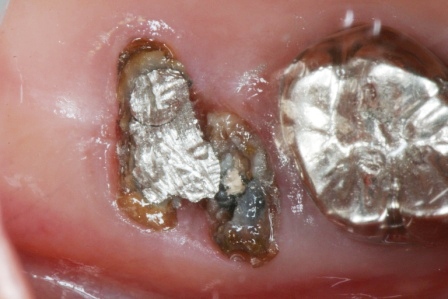

50代女性、右上7、口臭が気になる。

元々つながっていた歯根が3つに分離していて、近心根はコアがダツリしています。

メタルコアはピンで留める分割コアと、凝った作りです。

冠を外して、コアを削り取って、ピンも削り取って、虫歯も削り取って少しだけきれいにしました。